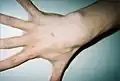

Hand of 37-year-old patient showing interdigital webbing